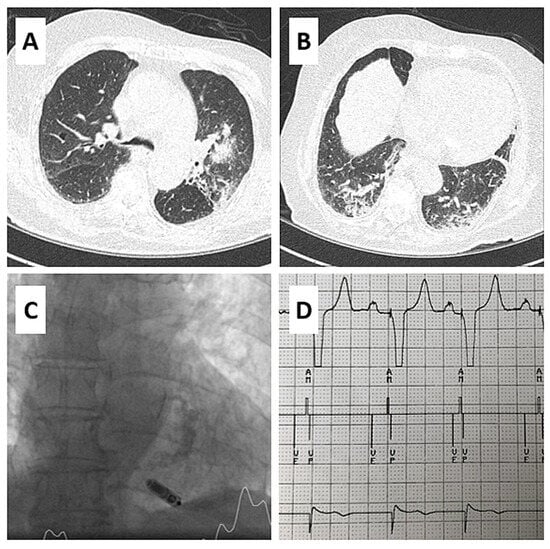

AV Synchronous Pacing with a Single-Chamber Leadless Pacemaker in a Patient with COVID-19 and Complete AV Block